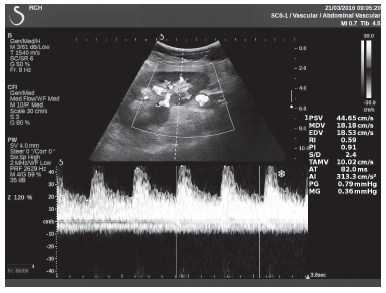

Клинический пример из первой группы. Пациент М., с хронической почечной недостаточностью. Трансплантация почки произведена от живого родственного донора. Трансплантат находится в правой подвздошной области. При нормальном функциональном состоянии трансплантата, показатели цветовой и спектральной допплерографии оценивались как удовлетворительные, с индексом резистентности не более 0,60 (рис. 1); показатели жесткости паренхимы почечного трансплантата при УЭСВ на различных участках составили от 20,05 до 29,18 кПа (рис. 2-4).

Рисунок 1. Ультразвуковое исследование в режиме цветовой и спектральной допплерографии в междольковых и сегментарных артериях у пациента М. Показатели кровотока в данном случае не изменены